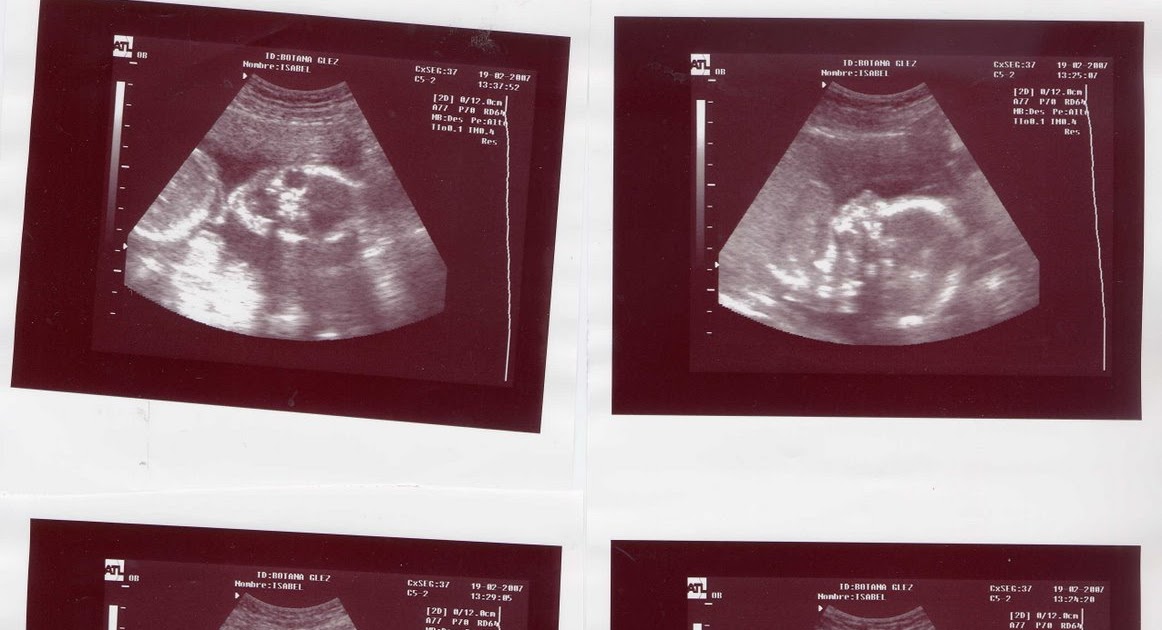

Mi embarazo ECOGRAFIA DE 20 SEMANAS

La ecografía morfológica o ecografía de las 20 semanas. Eco Emotions 5D

La ecografía morfológica de las 20 semanas La aventura de mi embarazo

Ecografía de las 20 semanas Servicio de Ginecología y Obstetricia del Hospital Clínico de Valencia

En la semana 20 de embarazo, toda su columna ya está casi recta y la ecografía también revelará todas sus vértebras. A partir de ahora, el peso del bebé aumentará más de diez veces y llegará a medir el doble de lo que mide en estos momentos. A pesar de que el líquido amniótico que lo rodea distorsiona un poco los sonidos, el feto ya.